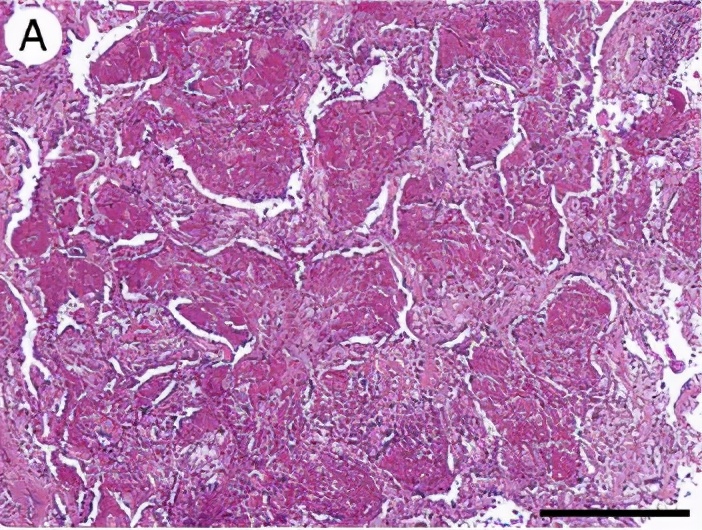

之后进行病理检查:肉芽肿,纤维化,细支气管炎,病理结果符合过敏性肺炎的表现,但是还没有问出病史。

ZYM:肉芽肿,NSIP-like,细支气管炎亚急性表现细胞性NSIP、细支气管炎和肉芽肿三联征,出现<75%。

CLX:慢性HP,纤维化比较明显,肺结构也被破坏,肉芽肿,UIP-lilke,细支气管炎。

慢性HP:气道中心性肺纤维化较明显。

所以病理改变特点可以表现为不同形式:

HP可能代表部分病理证实的NSIP、BOOP、UIP,所以我们考虑一下,有时我们诊断为特发性间质性肺炎,如果把原因都问出来,是不是有可能就是过敏性肺炎呢?

下图都是肉芽肿性疾病,但是结节病的肉芽肿是边界非常清楚的间质性结节,过敏性肺炎的肉芽肿的边界比较模糊。